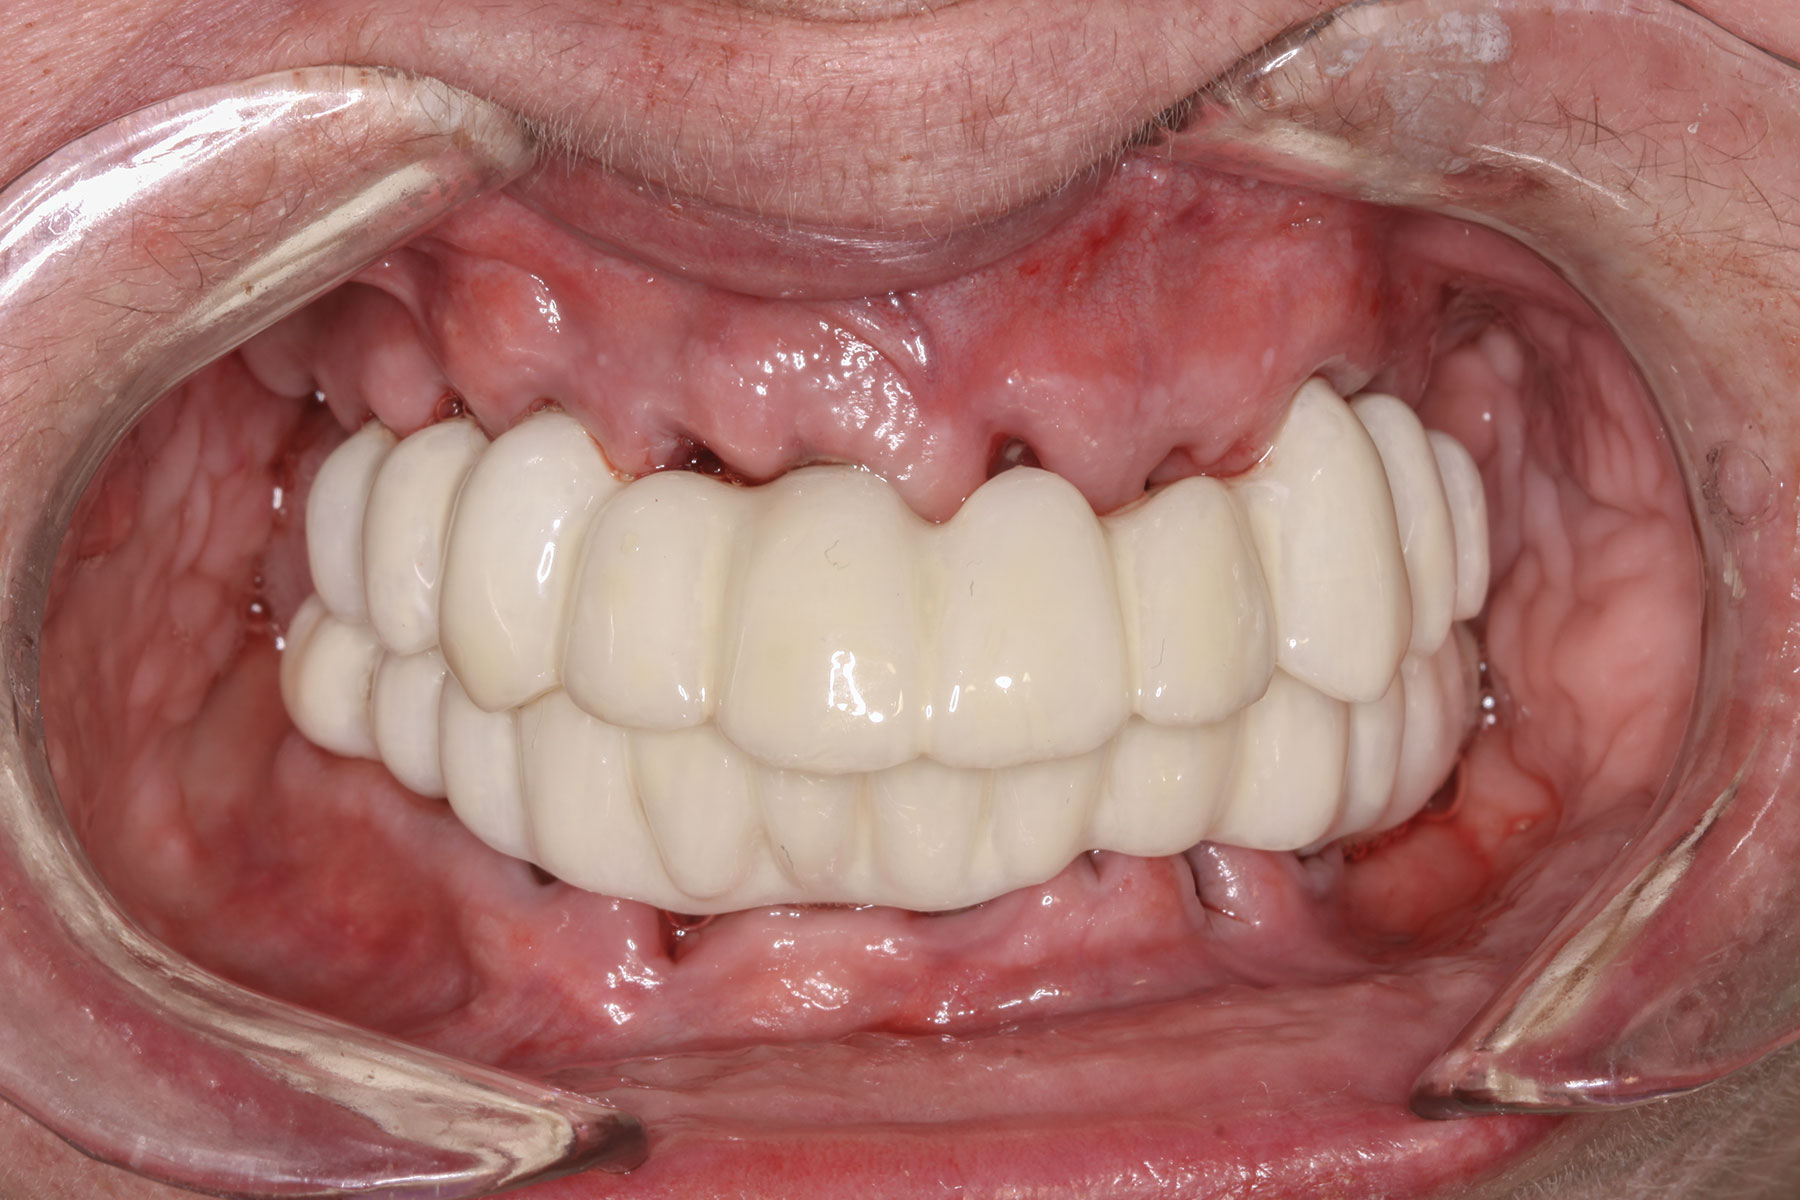

The completed provisional prosthesis was then screwed onto the multi-unit abutments with titanium screws and torqued to 20 Ncm. Screw-access holes were filled, and no occlusal adjustment was necessary. The fit of the prosthesis was precise and stable, and the patient's phonetics were ideal. The patient was overwhelmed by the significant esthetic improvement with this set of teeth in place (Figure 6 through Figure 8).

Fig 7. Maxillary provisional prosthesis seated on implants, on the day of surgery.

Figure 7

Fig 8. Implants and provisional maxillary prosthesis in place, the same day as surgery.

Figure 8